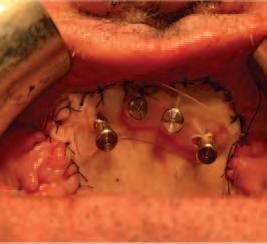

The zygomatic implant perforated (ZIP) flap for rehabilitation of patients with midfacial oncology defects: a report of three cases B. Martin, E. Cotter, C. Bowe, J.E. O’Connell

145 CLINICAL FEATURE

This edition also includes a peer-reviewed case report on zygomatic implant perforated flaps for patients with midfacial oncology defects by Dr Brian Martin et al., and in our clinical feature, Drs Marchini and Ettinger look at the very pertinent issue of maximising dental attendance in our older population.